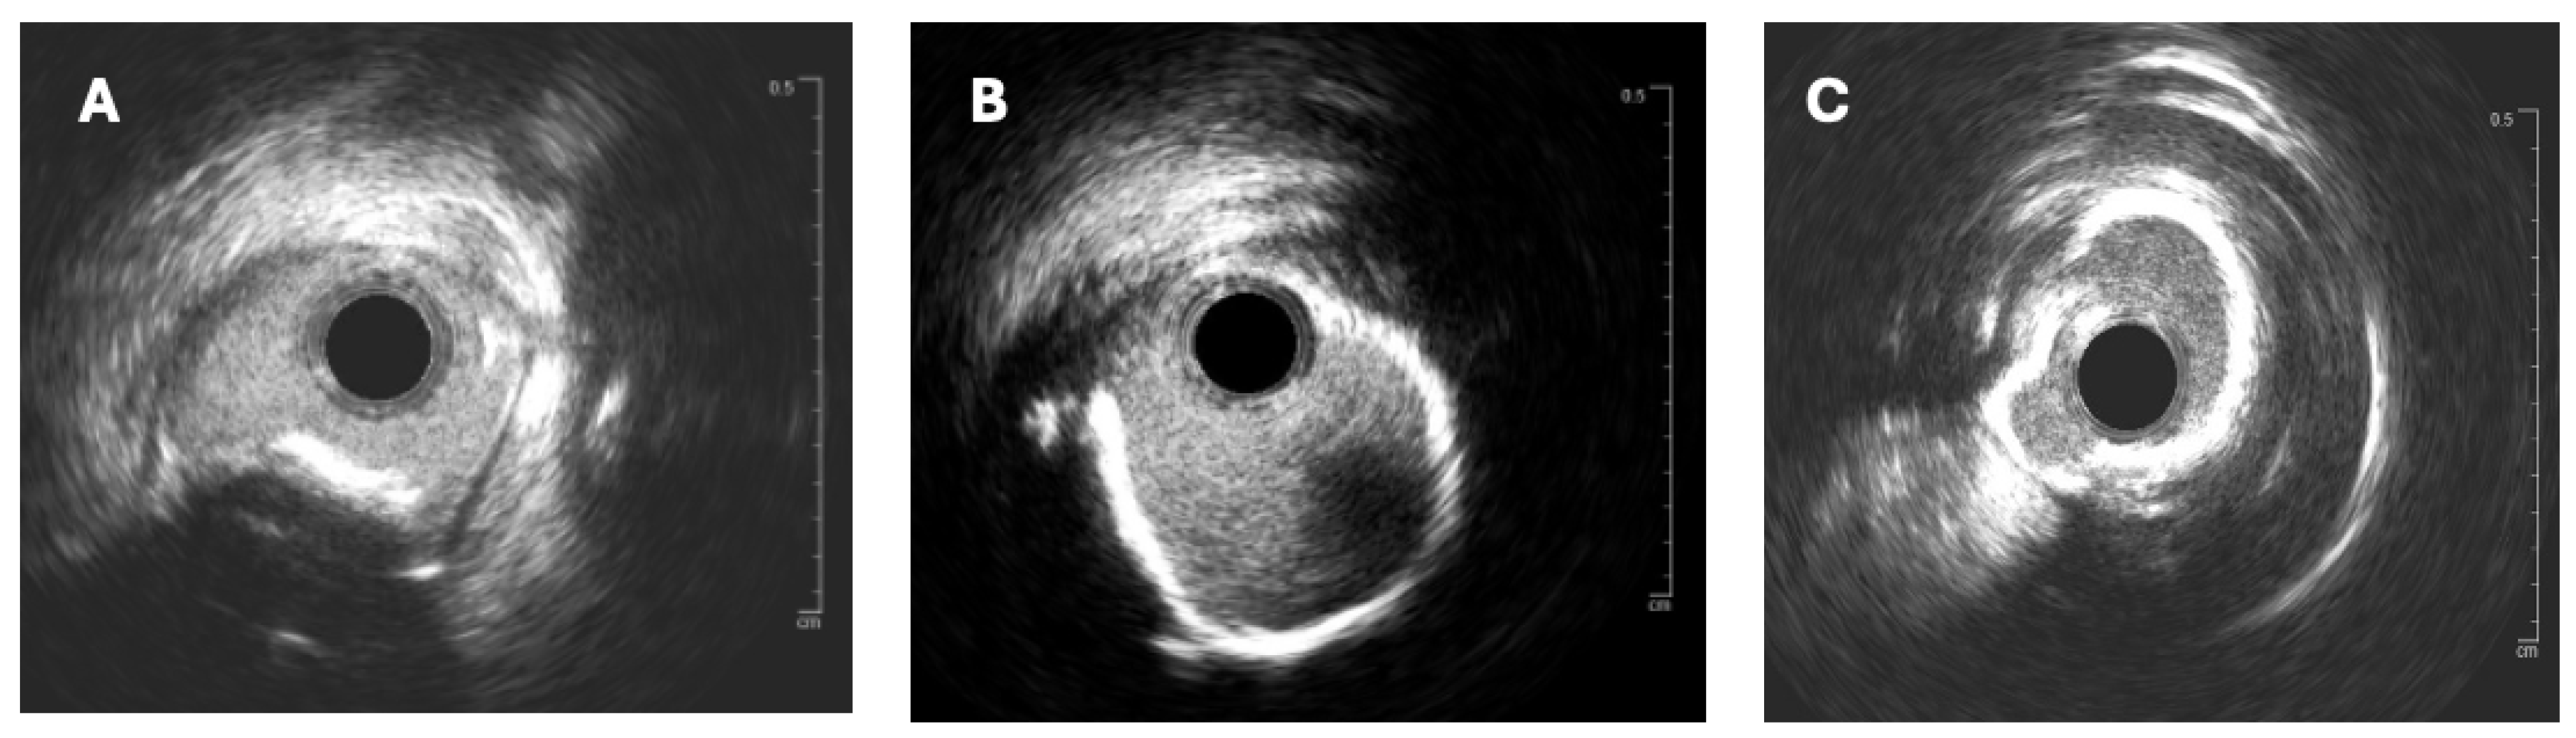

The effective execution and operation of intracoronary imaging modalities during these procedures improve both procedural and long-term clinical outcomes, particularly in intravascular ultrasound (IVUS) (Figure 6 and Figure 7) and optical coherence tomography (OCT) (Figure 8 and Figure 9), where coronary lesion morphology and mapping facilitate better PCI procedural planning [46]. Both IVUS and OCT can detect, localize, and quantify coronary calcification. Notably, OCT can visualize the calcified plaque without producing visual imaging artifacts, thereby minimizing observational scatter, and can evaluate calcium thickness more accurately than IVUS.

Intravascular ultrasound (IVUS) can provide information related to the arc, length, and superficial/deep texture of calcified plaques, but is restricted to the higher capabilities and superiority of optical coherence tomography (OCT), which can provide more than 10 times the spatial resolution of calcium deposits in the coronary walls when compared to the former imaging modality [33]. Both OCT and IVUS have demonstrated that CNs frequently present as eccentric, protruding calcific deposits disrupting luminal geometry. This morphology is associated with difficult wire passage, balloon slippage, and high rates of incomplete stent expansion, all of which translate into increased procedural complexity and suboptimal clinical outcomes [34,35].